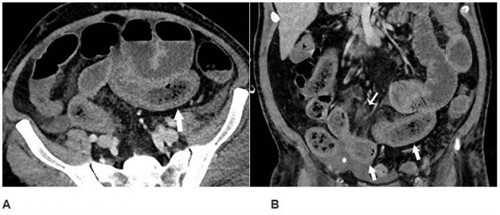

Identifican una biomolécula que puede mejorar la reparación del revestimiento del intestino Castellón Plaza